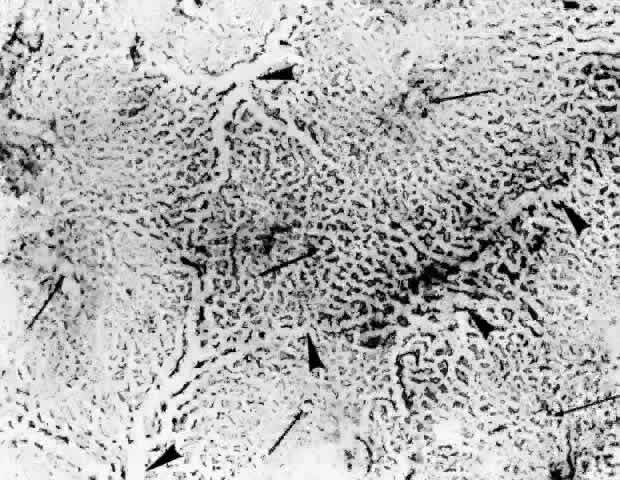

histologic sections (Figs. 21, 22, and 23). They described the overall appearance of the posterior choriocapillaris

arteriole would function as an end-arteriole.  Fig. 21. Flat preparation of choriocapillaris, posterior pole. A. Arrowheads indicate oval openings to the postcapillary venules. The area

around the precapillary arteriole (white-bordered arrow) is stained more heavily because of residual subcapillary collagen. (PAS, × 180; AFIP

Neg 74-9984) B. Postcapillary venules (arrowheads) form an irregular ring bordering the capillaries that radiate from the

precapillary arteriole (white-bordered arrows), thus outlining a single lobule. The capillaries are broader and clearer

near the venules because of less subcapillary collagen. (PAS, × 100, AFIP

Neg 74-10240) C. The openings of the postcapillary venules (as shown above) are connected

with black lines; they demarcate adjoining lobules in the choriocapillaris. Capillaries

from adjoining lobules enter the intervening venules. The

lobules form a mosaic of adjoining vascular beds. Precapillary

arterioles are indicated by white-bordered arrows. (PAS × 55; AFIP

Neg 74-9985) Fig. 21. Flat preparation of choriocapillaris, posterior pole. A. Arrowheads indicate oval openings to the postcapillary venules. The area

around the precapillary arteriole (white-bordered arrow) is stained more heavily because of residual subcapillary collagen. (PAS, × 180; AFIP

Neg 74-9984) B. Postcapillary venules (arrowheads) form an irregular ring bordering the capillaries that radiate from the

precapillary arteriole (white-bordered arrows), thus outlining a single lobule. The capillaries are broader and clearer

near the venules because of less subcapillary collagen. (PAS, × 100, AFIP

Neg 74-10240) C. The openings of the postcapillary venules (as shown above) are connected

with black lines; they demarcate adjoining lobules in the choriocapillaris. Capillaries

from adjoining lobules enter the intervening venules. The

lobules form a mosaic of adjoining vascular beds. Precapillary

arterioles are indicated by white-bordered arrows. (PAS × 55; AFIP

Neg 74-9985)